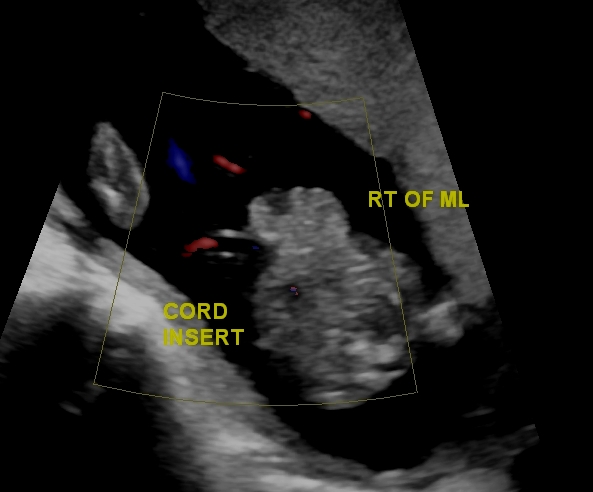

Omphalocele

An omphalocele is a persistent bowel herniation into umbilical cord.

Omphaloceles are caused by the failure of herniated intestines to return to the body cavity during development.

An omphalocele consists of a peritoneum and amnion of the umbilical cord covering the abdominal contents.